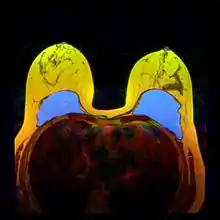

Silicone implant rupture can be evaluated using magnetic resonance imaging; from the long-term MRI data for single-lumen breast implants, the European literature about second generation silicone-gel breast implants (1970s design), reported silent device-rupture rates of 8–15 per cent at 10-years post-implantation (15–30% of the patients).[46][47][48][49]

The study Safety and Effectiveness of Mentor’s MemoryGel Implants at 6 Years (2009), which was a branch study of the U.S. FDA's core clinical trials for primary breast augmentation surgery patients, reported low device-rupture rates of 1.1 per cent at 6-years post-implantation.[50] The first series of MRI evaluations of the silicone breast implants with thick filler-gel reported a device-rupture rate of 1 percent, or less, at the median 6-year device-age.[51] Statistically, the manual examination (palpation) of the woman is inadequate for accurately evaluating if a breast implant has ruptured. The study, The Diagnosis of Silicone Breast implant Rupture: Clinical Findings Compared with Findings at Magnetic Resonance Imaging (2005), reported that, in asymptomatic patients, only 30 per cent of the ruptured breast implants are accurately palpated and detected by an experienced plastic surgeon, whereas MRI examinations accurately detected 86 per cent of breast implant ruptures.[52] Therefore, the U.S. FDA recommended scheduled MRI examinations, as silent-rupture screenings, beginning at the 3-year-mark post-implantation, and then every two years, thereafter.[23] Nonetheless, beyond the U.S., the medical establishments of other nations have not endorsed routine MRI screening, and, in its stead, proposed that such a radiologic examination be reserved for two purposes: (i) for the woman with a suspected breast implant rupture; and (ii) for the confirmation of mammographic and ultrasonic studies that indicate the presence of a ruptured breast implant.[53]

Furthermore, The Effect of Study design Biases on the Diagnostic Accuracy of Magnetic Resonance Imaging for Detecting Silicone Breast Implant Ruptures: a Meta-analysis (2011) reported that the breast-screening MRIs of asymptomatic women might overestimate the incidence of breast implant rupture.[54] In the event, the U.S. Food and Drug Administration emphasised that “breast implants are not lifetime devices. The longer a woman has silicone gel-filled breast implants, the more likely she is to experience complications.”[55]